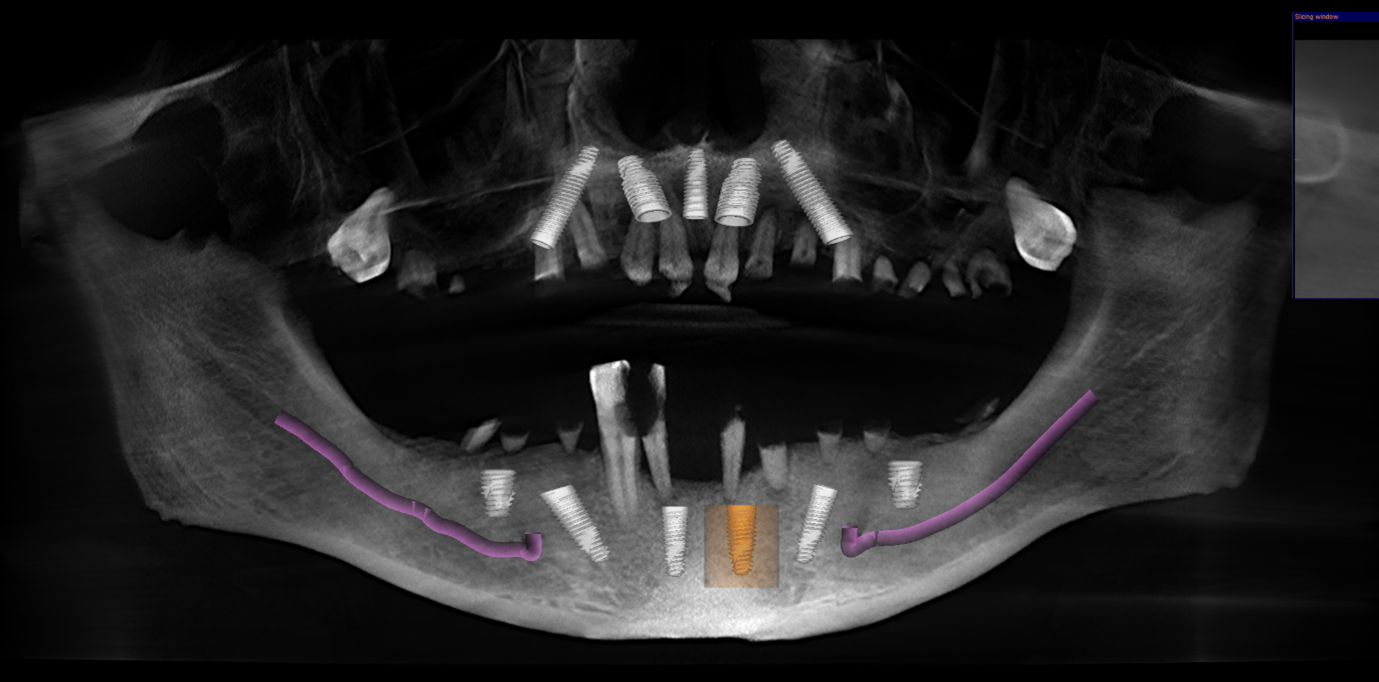

We carried out a comprehensive clinical assessment and gathered detailed diagnostic records, including:

• clinical photographs

• intraoral scans and photos

• OPG x-ray

• CBCT scan

• digital implant planning records

These records allowed us to carefully evaluate bone levels, gum health, and ideal implant positioning.

Although the patient showed moderate bone loss in certain areas and signs of previous chronic infections, his overall bone quality remained suitable for implant treatment. Importantly, there was no active infection at the time of surgery.

• placement of 5 implants in the upper jaw

• placement of 6 implants in the lower jaw

She emphasises that detailed CBCT planning is one of the most critical aspects of treatment, as it ensures precision, reduces risk, and supports long-term success.